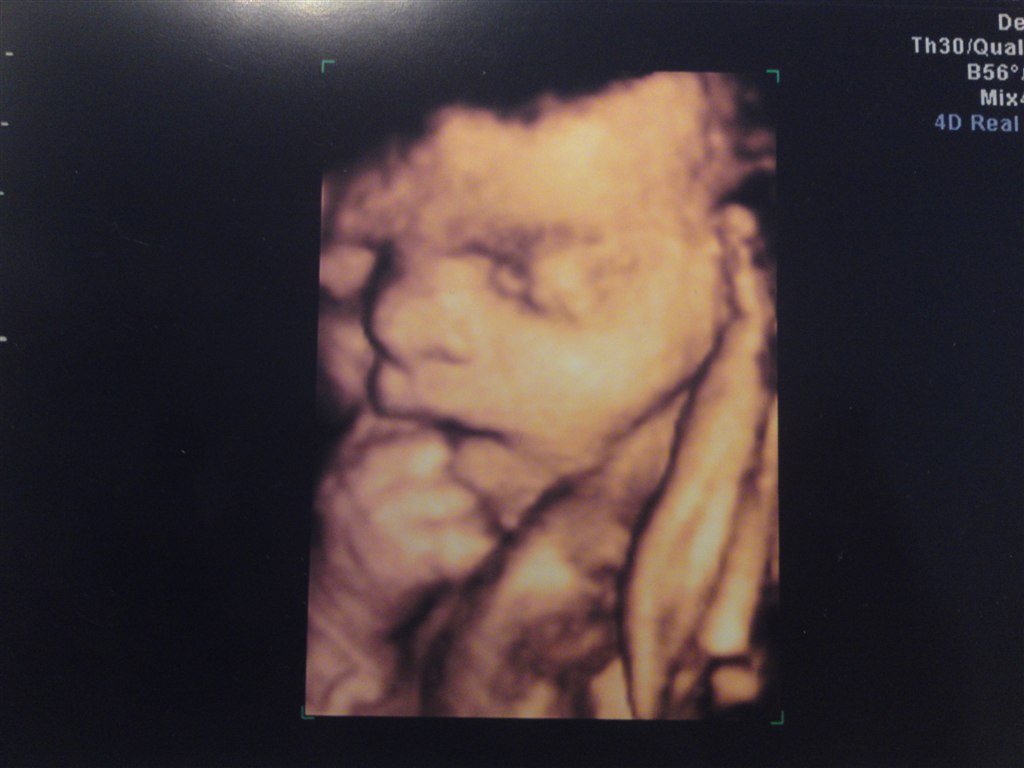

Syntes det er vildt! elsker 3d..Håber jeg kommer til at opleve det igen en dag..Peter sys det ser råklamt ud så tager bare en veninde med

Syntes oplevelsen er helt fantastisk og når man har muligheden for at lure den kage der er i ovnen..så kan jeg sgi ikk la være